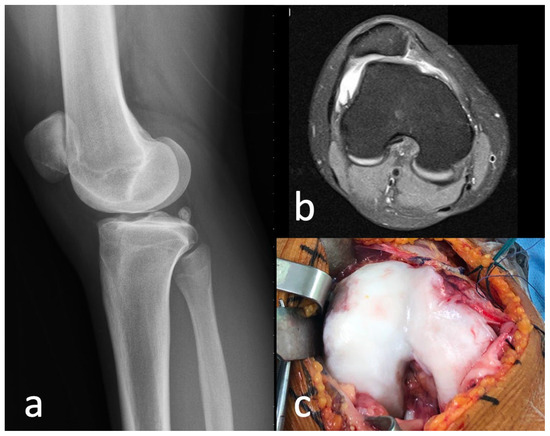

2.1. Case

2.2. Surgical Procedure